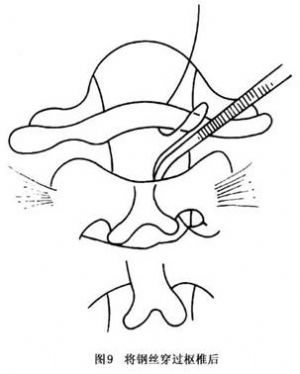

14.3.3 Gallie手术

Gallie手术多用于寰枢关节脱位明显者,如图8~10所示。先切取植骨块将其修成相应大小及所需的形状,之后将钢丝穿过寰椎后弓,再穿过枢椎两侧后弓下方收紧钢丝,使骨块嵌于颈1、2棘突之间即达复位及融合目的。本法的骨融合成功率较前者低,但对转颈活动影响较少。